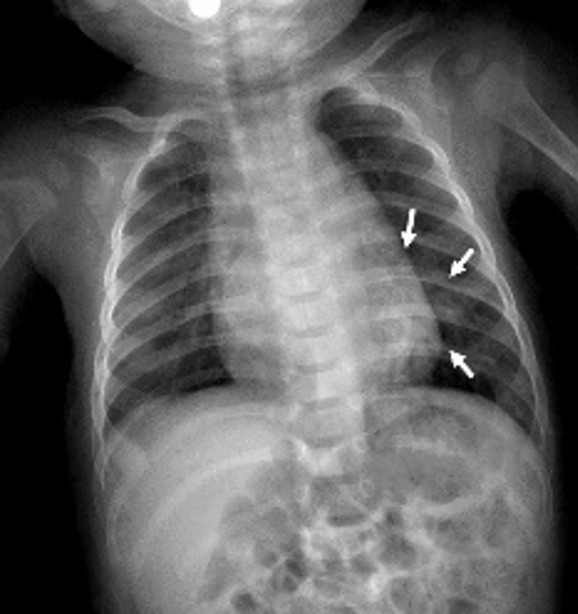

A 5-month-old infant was referred to our hospital after a suspected cardiac murmur was detected during a routine health check-up. Born via cesarean section at 39 weeks, the patient had no history of neonatal hospitalization, respiratory distress, or episodes of infection or bronchiolitis. Routine laboratory tests, including a complete blood count and assessments of kidney and liver function, were all normal. Chest X-ray revealed ground-glass opacities in the left upper and middle lung zones and opacification in the left lower zone (Figure 1). Thoracic CT and CT angiography were performed for further evaluation, with CT angiography demonstrating an aberrant vessel originating from the supradiaphragmatic descending aorta (Figure 2). This large systemic artery had three branches supplying the left lower lobe. Venous drainage from the affected lung parenchyma occurred via a dilated, tortuous left inferior pulmonary vein into the left atrium (Figure 3). No parenchymal abnormalities were observed, and the left lower lobe bronchus and its segmental branches appeared normal. These findings supported a diagnosis of pseudosequestration, as the affected lobe maintained a connection with the bronchial tree, differentiating it from true sequestration.